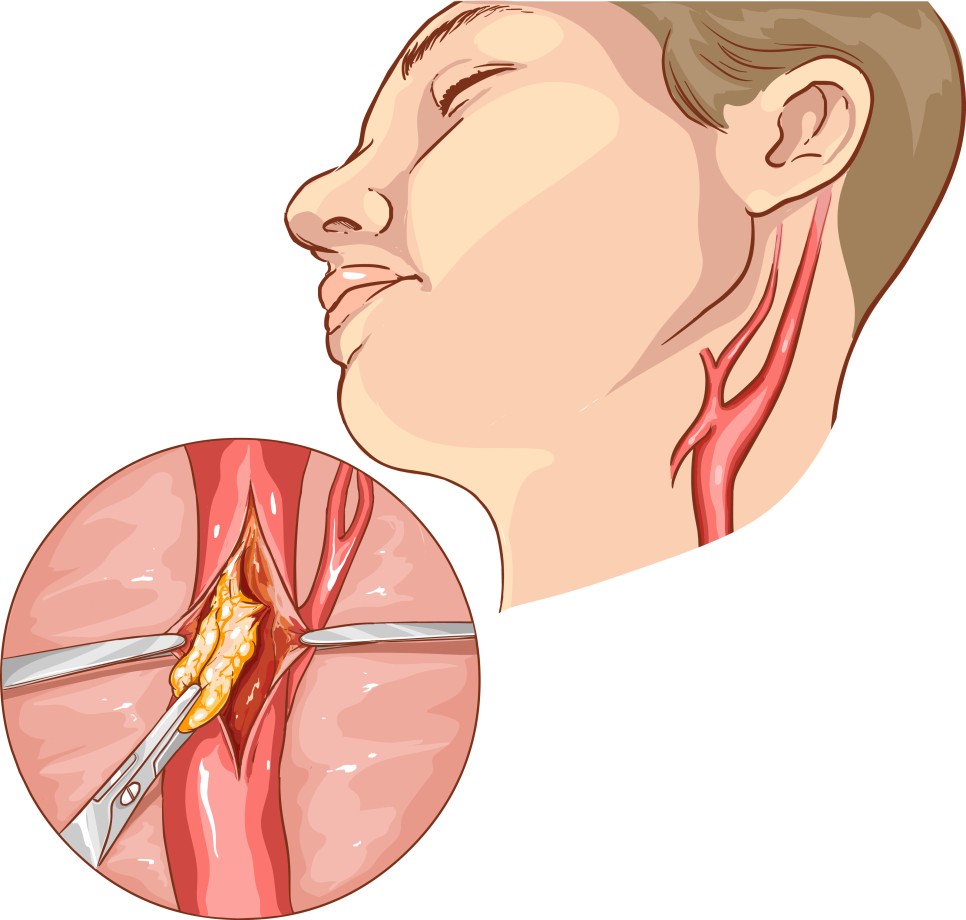

경동맥 협착증 수술은 경동맥 내막 절제술을 통해 동맥 경화의 찌꺼기를 제거합니다. 전신 마취가 필요하지만 동맥 경화의 찌꺼기를 직접 제거하기 때문에 재협착률은 낮은 편입니다.